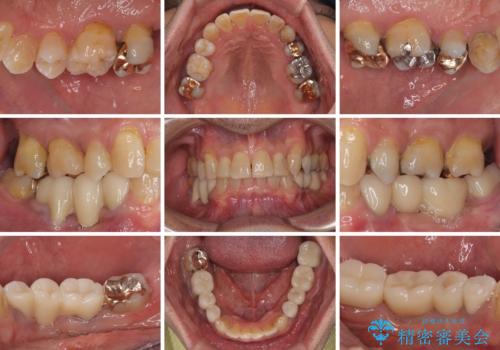

- 下顎両側の欠損と上顎前歯のデコボコを気にして来院された患者様です。

デコボコは今まで気にせずにいたそうですが、奥歯の欠損改善を機に、矯正治療に興味があるので、相談したいとのことでした。

奥歯に欠損が多く、矯正治療はやや難航することが予想されますが、患者様の希望もあり、上顎左右小臼歯を1本ずつ抜歯し、ワイヤー装置にて矯正治療を行うこととしました。

矯正歯科治療を行うに当たり、痛みや違和感を感じている歯の根管治療を行い、矯正治療中にインプラント埋入し、補綴治療と矯正治療を同時に終了できるように進めて行くこととしました。

銀歯やむし歯治療されている歯を抜歯する治療計画としたため、やや時間はかかりましたが、治療後の仕上がりには大変満足していただけました。